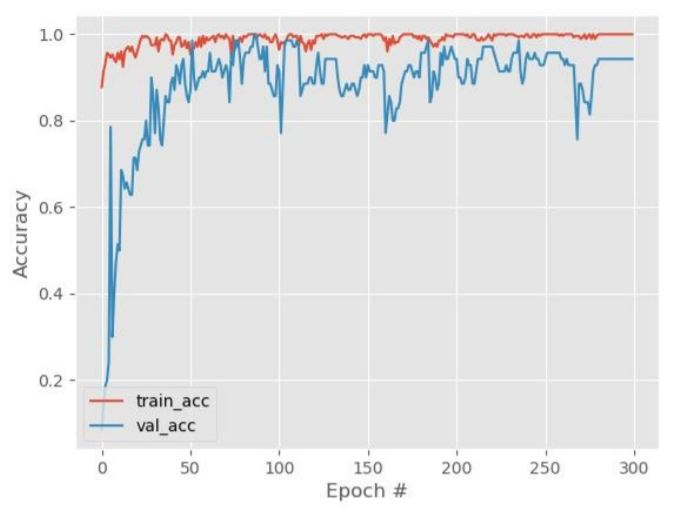

Result

AlexNet was seen to give the best performance with a huge accuracy of 98.57%. Not only the accuracy is high, but the losses are low as well. The AlexNet model helped hugely in predicting accurately a person affected by Alzheimer’s.